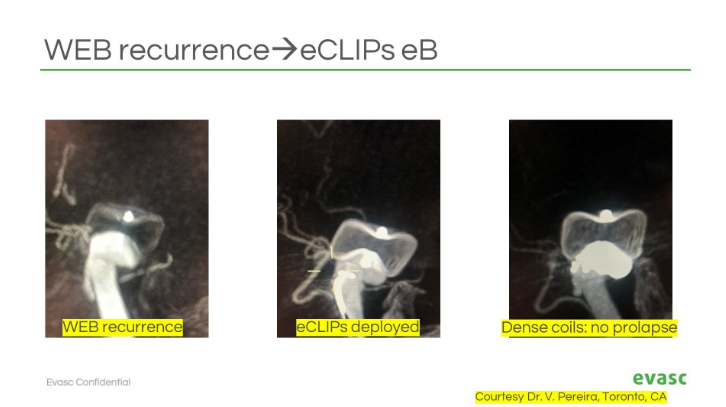

Treating wide-neck bifurcation #aneurysms? #eCLIPs could be the solution. Join Dr. Jan-Hendrik Buhk in this ESMINT Society webinar on how eCLIPs works + where it fits in complex cases. Watch: esmint.eu/video/wide-nec… For more information: bit.ly/contact-evasc or DM us.